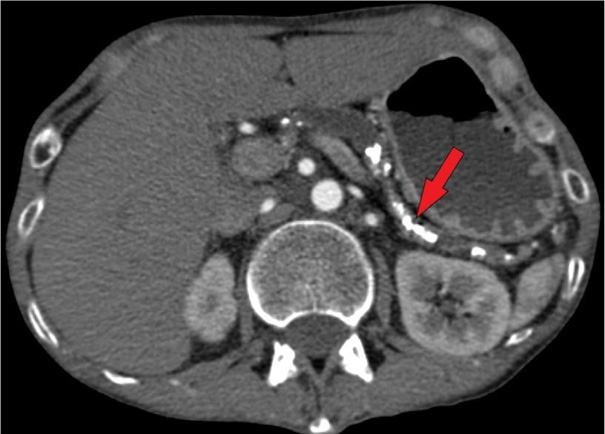

Physical examination revealed bilateral parotid hypertrophy, restricted jaw movement, and abdominal tenderness in both upper quadrants. The patient’s body mass index (BMI) was only 11.97 kg/m2 (Height = 171 cm; Weight = 35 kg). The psychiatrists suspected bulimia nervosa and anorexia nervosa, manifesting along with chronic idiopathic pancreatitis with pancreatic insufficiency. That was because of the patient’s tremendously low BMI, which is frequently seen in eating disorders. Parotid gland enlargement and tenderness also supported this theory because it resembled a typical ‘bulimia face’ appearing with ‘chipmunk-like’ sialadenosis. However, the patient had no history of eating disorders or binge eating as confirmed before. Laboratory tests showed hypokalemia, elevated α-amylase concentration of 385 U/L (cf. normal: 28–100 U/L), normal pancreatic amylase levels, and an increase of bile acids (20 µmol/L). Although in ultrasound (US) and computed tomography (CT) imaging no significant damage in the bile ducts was seen, the bile acid elevation and marked itchiness indicated cholangitis. Abdominal US revealed a heterogeneous pancreas with parenchymal calcifications and a dilated pancreatic duct (0.9 cm wide), containing a 0.5 cm intraductal stone in the pancreatic head. US showed a heterogeneous parotid gland structure, with the right parotid gland measuring 5.2 × 2.9 cm and the left 4.9 × 2.8 cm. Abdominal and pelvic CT imaging revealed multiple pancreatic calcifications, up to 0.8 cm dilated pancreatic duct, consistent with chronic pancreatitis (Fig. 1). A review of previous laboratory findings indicated that elevated IgG4 levels (up to 2 g/L) had been present since 2018.

Pancreatic imaging typically reveals generalized or segmental pancreatic enlargement, coupled with the loss of normal lobularity and diffuse stenosis of the pancreatic duct [1]. Our patient’s abdominal US and CT revealed dilation of the pancreatic duct due to intraductal concrements.